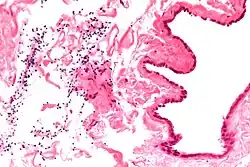

The primary care physician may diagnose and manage benign causes of scrotal masses such as hydrocele, varicocele and spermatocele. However, if a "must not miss" diagnosis related to testicular masses such as testicular torsion, epididymitis, acute orchitis, strangulated hernia and testicular cancer is suspected, the family physician must refer to a urologist.[19] Finding a painless, cystic mass at the head of the epididymis that is clearly separate from the testicle can indicate a spermatocele. Shining a light through the mass, a process known as transillumination, can also help differentiate between a fluid-filled cyst and a tumor, which would not allow as much light to pass.[20] If uncertainty exists, ultrasonography of the scrotum can confirm the presence of a spermatocele.[7] The location and history of any scrotal masses are crucial in determining whether or not the mass is benign or malignant.[21] Lab tests such as a complete blood count (CBC test) or urine test can also be conducted to check for any possible infection or signs of inflammation.[22]

Spermatoceles come in varying sizes and shapes. Some spermatoceles are very small and can only be detected through an ultrasound. More commonly seen are spermatoceles that are a pea-sized lump. They tend to form above or behind a testicle and have a shape and size that looks like a pea. Larger growths have been reported to look similar to a third testicle and can be very discomforting.[22] For those who are affected with large spermatoceles, some have reported feeling pain, heaviness, and fullness in the affected testicle.[20]